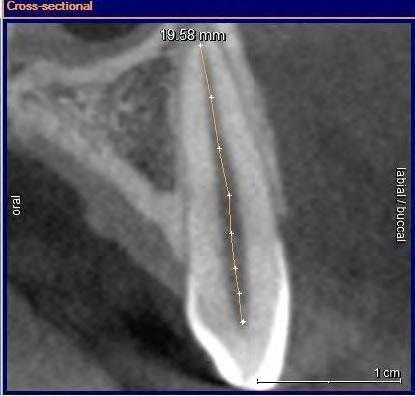

Описаны варианты раздвоения канала нижней челюсти (НЧ), которые были выявлены как случайные находки при конусно-лучевой компьютерной томографии челюстно-лицевой области пациентов, обращавшихся в медицинские центры за стоматологической помощью. Выявленные добавочные каналы в теле НЧ начинались от верхней стенки нижнечелюстного канала и имели небольшую протяженность. Они заканчивались в ретромолярной области, направлялись к корням зубов или ориентировались параллельно основному каналу НЧ.

Рентгенологическое исследование проводилось на аппарате Galileos GAX5 («Sirona Dental Systems, Bensheim», Germany). Анализ полученных данных проводился по традиционной методике, предусматривающей последовательное изучение сначала срезов в 3 взаимно перпендикулярных проекциях (окно мультипланарной реконструкции), затем срезов, расположенных продольно и поперечно относительно зубной дуги (в окне «Панорама»), а также томограмм произвольной кросс-секции, оптимальной для получения изображений анатомических объектов соответственно их пространственному положению. Оптимальными для визуализации вариантов ветвления канала НЧ являлись реформаты вдоль продольной оси ее тела, которые обозначаются по терминологии разработчиков аппарата как «касательные».

Пациентка Ф., 55 лет. С правой стороны на уровне угла челюсти от верхней стенки нижнечелюстного канала начинался дополнительный канал с поперечным диаметром 1,52 мм (рис. 3, а). Рис. 3. Дентальный канал нижней челюсти. а — КЛКТ пациентки Ф., 55 лет; б — КЛКТ пациентки К., 29 лет. 1 — канал НЧ; 2 — дентальный канал; 3 — подбородочное отверстие. Поперечный диаметр основного канала на этом же уровне — 2,70 мм. Дополнительный канал направлялся полого вперед и вниз параллельно основному каналу НЧ. В мезиальном направлении кортикализация стенок дополнительного канала постепенно уменьшалась, и достоверно проследить его ход удалось до уровня зуба 4.7. Описанная картина характерна для дентального канала (3-й тип раздвоенного канала НЧ). С левой стороны визуализация дополнительного канала была недостоверной: выявлялось линейное просветление такой же локализации и направления, как с правой стороны, но картины трубчатого образования не выявлено, вероятнее всего — вследствие недостаточной кортикализации его стенок.

У пациентки К., 29 лет, с левой стороны обнаружен дентальный канал (см. рис. 3, б). В месте отхождения он имел вертикальный диаметр 1,35 мм (приблизительно в 3 раза меньше вертикального диаметра канала НЧ на этом же уровне), направлялся вперед и вниз, располагаясь параллельно основному нижнечелюстному каналу, и на уровне медиального корня зуба 3.7 круто поднимался вверх. Дентальный канал переставал идентифицироваться на уровне средней трети корня второго нижнего левого моляра. С правой стороны раздвоения канала НЧ не выявлено.

Канал НЧ при типичной локализации визуализируется в виде трубчатого костного образования, стенки которого представлены тонкими линейными затемнениями кортикальных пластинок, а содержимое канала отображается в виде интенсивного просветления. Калибр канала постепенно уменьшается в мезиальном направлении. Достоверным признаком наличия дополнительного канала является продолжение в его стенку кортикальной пластинки основного канала. Это дает возможность проследить дополнительный канал на всем его протяжении. У места его начала канал НЧ, как правило, имеет локальное расширение. Дополнительные каналы обычно отходят от верхней стенки канала НЧ и имеют небольшую протяженность.

Анатомические варианты локализации каналов в теле НЧ многообразны. Тем не менее обнаружение основного и добавочного канала в месте предстоящих манипуляций предопределяет эффективность дентальной имплантации и других хирургических операцией на НЧ.